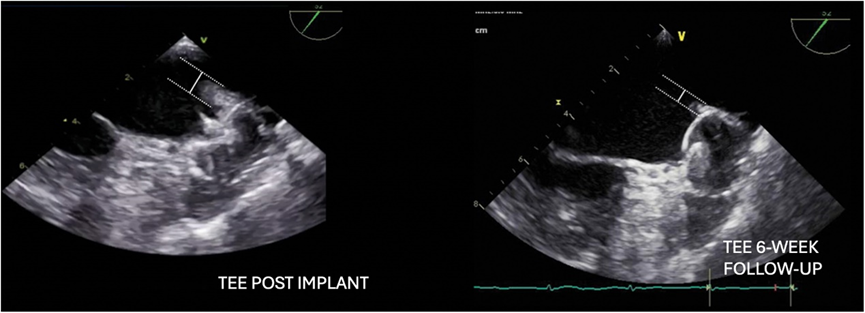

最后一次消融后,通过电复律恢复窦性心律。PV 传入阻滞通过PFA消融导管Olive橄榄型在肺静脉口部起搏确认。然后插入经食道超声心动图 (TEE) 探头来引导左心耳封堵术。有趣的是,观察到LSPV和LAA之间的嵴部肿胀,但是水肿似乎不涉及着陆区的水肿,因此我们继续进行左心耳封堵术手术。

在LSPV中,将 Faradrive® 鞘管通过导丝置换成 Boston Scientific双向可调弯 14Fr 输送鞘管。使用 6 Fr猪尾巴导管将WATCHMAN14Fr 输送鞘管引导至 LAA,并在RAO30°、CRA15° 和CAU20° 角度下进行造影。造影或 TEE 上的 LAA 着陆区最大直径为 22.8 mm(图1),因此选择了WATCHMAN FLX™ 27 mm封堵器。该封堵器在LAA中推送(图 2),并且可以在第一次尝试时成功植入,而无需重新定位。在多普勒序列中,没有观察到残留漏。患者出院时接受了双重治疗,即每日两次服用150mg达比加群作为直接口服抗凝剂 (DOAC) + 阿司匹林,并计划在手术后 6 周进行TEE随访。有趣的是,TEE 显示嵴部部水肿完全消退,封堵器近端轻微移动。压缩保持22mm,封堵令人满意,因此DOAC治疗(每日两次服用150mg达比加群)中断,继续服用阿司匹林。在 6个月的随访期间,未记录到中风或出血,也未记录到复发的房颤。

已经报道过同时进行左心耳封堵术和 PVI射频消融。在刚消融的组织上植入封堵器可能会因封堵器残余漏而导致封堵器脱落的风险。但是,Surpass Registry报告称,在45天的随访中,联合使用 PVI +左心耳封堵术与单独使用左心耳封堵术之间封堵器周围残余漏的程度没有差异。由于PFA具有不同的病变损伤机制,我们预计在 LAA 底部观察到的可能影响LAA封堵的水肿较少。如图3所示,事实并非如此:观察到 LAA-PV 嵴部(与组织直接接触的部位:Basket/Olive结构)明显水肿(0.8 厘米),与 6 周随访 TEE 图像相比尤其明显,6周水肿完全消退(0.4 厘米)。水肿被认为在口部而不是着陆区内,因此左心耳封堵术顺利完成。然而,仔细比较 TEE 后续图像后发现,封堵器近端微小倾斜,但并不影响LAA的密封性和封堵器的稳定性。

图表3手术期间观察到的 LAA-PV嵴部的经食道超声图像明显水肿(0.8 厘米),与 6 周随访经食道超声图像相比,水肿完全消退,水肿大小为 0.4 厘米